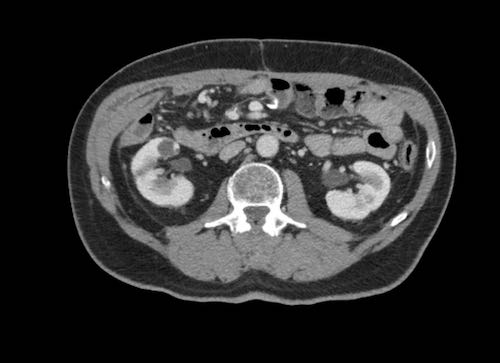

Ca lâm sàng 2

Cuộn qua các lát cắt.

Bạn có thể phát hiện tất cả các tổn thương cấy ghép phúc mạc không?

.jpeg)